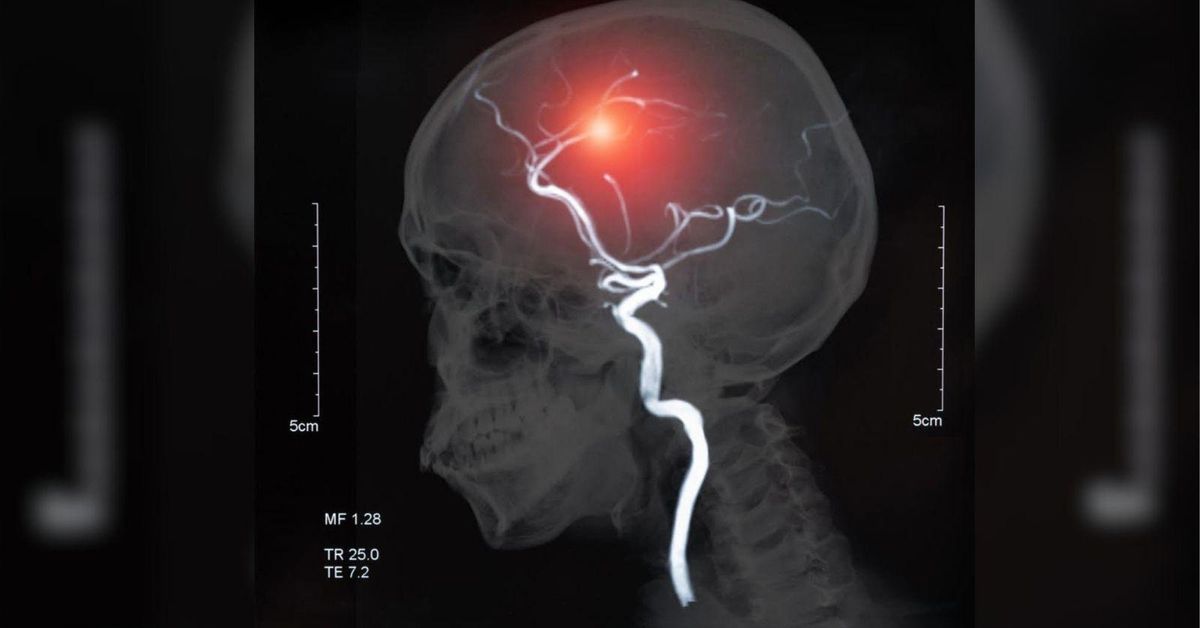

Especialistas alertan de tres picos de edad de incidencia del ictus isquémico

El ictus constituye una de las diez primeras causas de mortalidad infantil